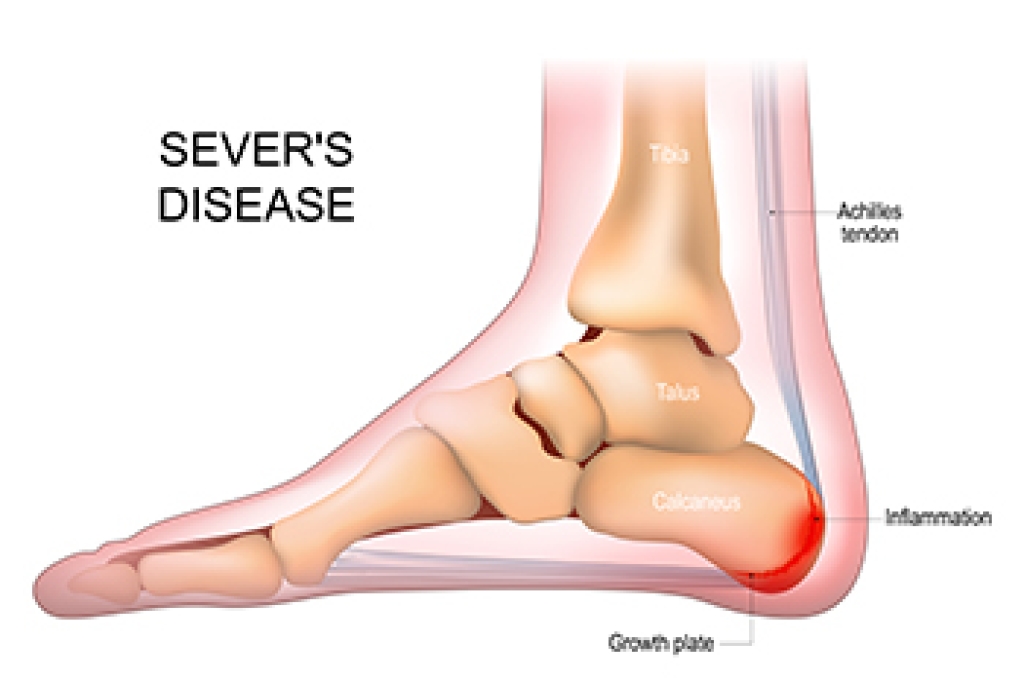

Anterior ankle impingement occurs when bone spurs or inflamed soft tissue at the front of the ankle joint cause pain. It is common during activities that involve dorsiflexion, such as walking uphill, squatting, or playing sports like soccer. These bone spurs, known as osteophytes, often form on the tibia or talus bones as a result of repeated bending or ankle sprains. Common symptoms of anterior ankle impingement include pain with activities that require bending or leaning forward. A podiatrist can use X-rays to detect bone spurs and MRI scans to assess inflammation or scarring. Non-operative treatments focus on wearing shoes with slightly elevated heels, modifying activities, using anti-inflammatory medications, and receiving corticosteroid injections. Strengthening exercises to prevent future problems are also helpful. In cases where conservative measures are ineffective, surgery may be required to remove the bone spurs and restore motion. If the front of your ankle consistently hurts, it is suggested that you schedule an appointment with a podiatrist for an exam, diagnosis and treatment.

Ankle pain is any condition that causes pain in the ankle. Due to the fact that the ankle consists of tendons, muscles, bones, and ligaments, ankle pain can come from a number of different conditions.

Causes

The most common causes of ankle pain include:

- Types of arthritis (rheumatoid, osteoarthritis, and gout)

- Ankle sprains

- Broken ankles

- Achilles tendonitis

- Achilles tendon rupture

- Stress fractures

- Bursitis

- Tarsal tunnel syndrome

- Plantar fasciitis

Symptoms of ankle injury vary based upon the condition. Pain may include general pain and discomfort, swelling, aching, redness, bruising, burning or stabbing sensations, and/or loss of sensation.

Due to the wide variety of potential causes of ankle pain, podiatrists will utilize a number of different methods to properly diagnose ankle pain. This can include asking for personal and family medical histories and of any recent injuries. Further diagnosis may include sensation tests, a physical examination, and potentially x-rays or other imaging tests.

Just as the range of causes varies widely, so do treatments. Some more common treatments are rest, ice packs, keeping pressure off the foot, orthotics and braces, medication for inflammation and pain, and surgery.